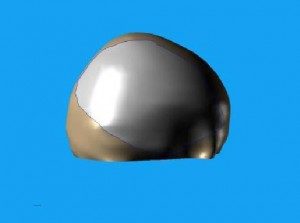

První snímky protézy